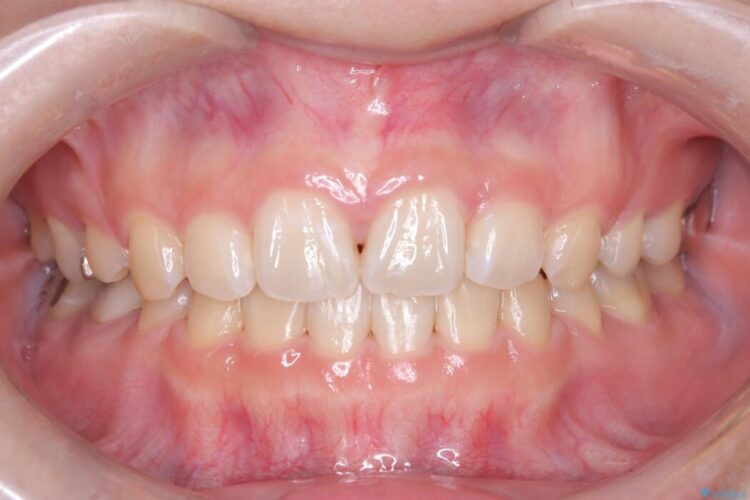

口元が突出していることを気にされご来院された患者様です。

今回の矯正治療では、前歯を大きく後退させるスペースを確保するため、計画通り上下左右の第一小臼歯を抜歯しました。

装置には、上顎には目立たない裏側矯正(舌側矯正)を、下顎には透明な審美ブラケットを使用するハーフリンガル矯正を採用しました。抜歯によってできたスペースを最大限に活用し、前歯を効率よく後方へ移動。治療の結果、口元の突出感が大幅に解消され、Eライン(横顔の美しさの基準)も改善しました。人目を気にすることなく治療を完遂し、自信の持てる美しい横顔を獲得していただけました。